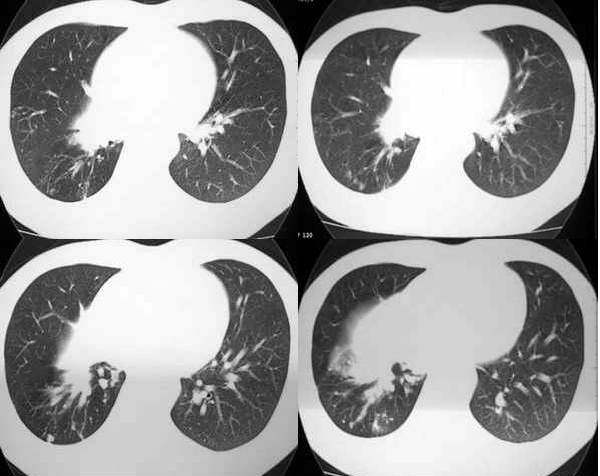

男,28岁,右胸不适,轻咳.余无特殊症状.请各位大侠发表见解

右肺下叶背段结核灶!肺门下方病灶没有传完整,不好说!看其形态,感觉象肺段实变,而且里面有散在点状钙化,不象是占位性病变.

28岁,右肺下叶背段病变,未见实质肿块,病灶内见钙化,及卫星灶,纵隔内有肿大淋巴结,结核吧,不象占位病变

右侧中间段支气管管壁增厚,管腔狭窄,形成块状软组织密度灶,右肺中叶膨胀不全,右肺下叶背段斑块状、片状阴影,且伴钙化,考虑:右侧中间段支气管内膜结核伴中叶不张、右肺下叶背段结核

右下叶背段及下叶内后基底段见斑点状及小片状影,有钙化。右下所谓的软组织密度影不在肺门,而是在下肺静脉层面以下,与膈相近,可能是横膈部分图像,图像没传完,易误导大家。综合考虑感染性病变(结核可能性大)

看斜裂应该是下叶膨胀不良,查右肺下叶支气管,除外占位。